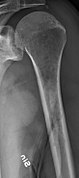

The diagnostic examination of a person with suspected multiple myeloma typically includes a skeletal survey. This is a series of X-rays of the skull, axial skeleton, and proximal long bones. Myeloma activity sometimes appears as "lytic lesions" (with local disappearance of normal bone due to resorption). And on the skull X-ray as "punched-out lesions" (pepper-pot skull). Lesions may also be sclerotic, which is seen as radiodense.[47] Overall, the radiodensity of myeloma is between −30 and 120 Hounsfield units (HU).[48] Magnetic resonance imaging is more sensitive than simple X-rays in the detection of lytic lesions, and may supersede a skeletal survey, especially when vertebral disease is suspected. Occasionally, a CT scan is performed to measure the size of soft-tissue plasmacytomas. Bone scans are typically not of any additional value in the workup of people with myeloma (no new bone formation; lytic lesions not well visualized on bone scan).

Multiple myeloma in the upper arm

Femur with multiple myeloma lesions

Same femur before myeloma lesions for comparison